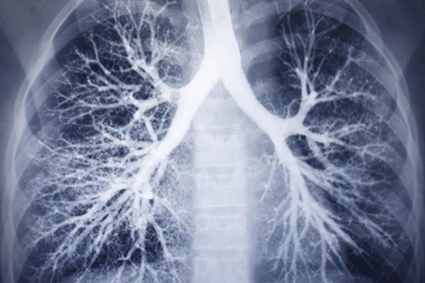

Chiết xuất trà xanh Epigallocatechin gallate (EGCG) là một chất chống ôxy hóa mạnh, có thể bảo vệ các tế bào cơ thể khỏi bị tổn hại vì nhiều bệnh. Các nhà khoa học Mỹ vừa phát hiện, EGCG có triển vọng giúp chống lại xơ phổi - tình trạng sẹo hóa mô phổi, làm giảm lượng khí ôxy mà cơ thể tiếp nhận và có thể diễn tiến thành bệnh suy phổi chết người.

Cụ thể, nhóm chuyên gia do Tiến sĩ Harold Chapman dẫn đầu tại Đại học California đã đối chứng tác động của EGCG trên 20 bệnh nhân Xơ hóa phổi vô căn (IPF, dạng xơ phổi phổ biến nhất), với phân nửa số bệnh nhân được cho dùng viên nang chứa 600mg EGCG/ngày và số còn lại không dùng thuốc này trong 2 tuần. Sau khi phân tích kết quả sinh thiết tế bào phổi của 2 nhóm, các chuyên gia nhận thấy nhóm dùng EGCG đã giảm nồng độ hai loại prôtêin có liên quan đến xơ phổi và xét nghiệm mẫu máu của họ cũng cho kết quả tương tự. Trái lại, nhóm đối chứng không có bất cứ cải thiện nào.